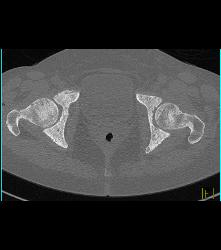

Psoas Abscess and IVC Clot